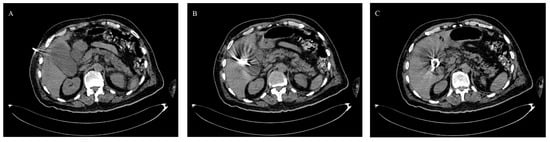

2.2. Procedure

2.3. Timing and Duration